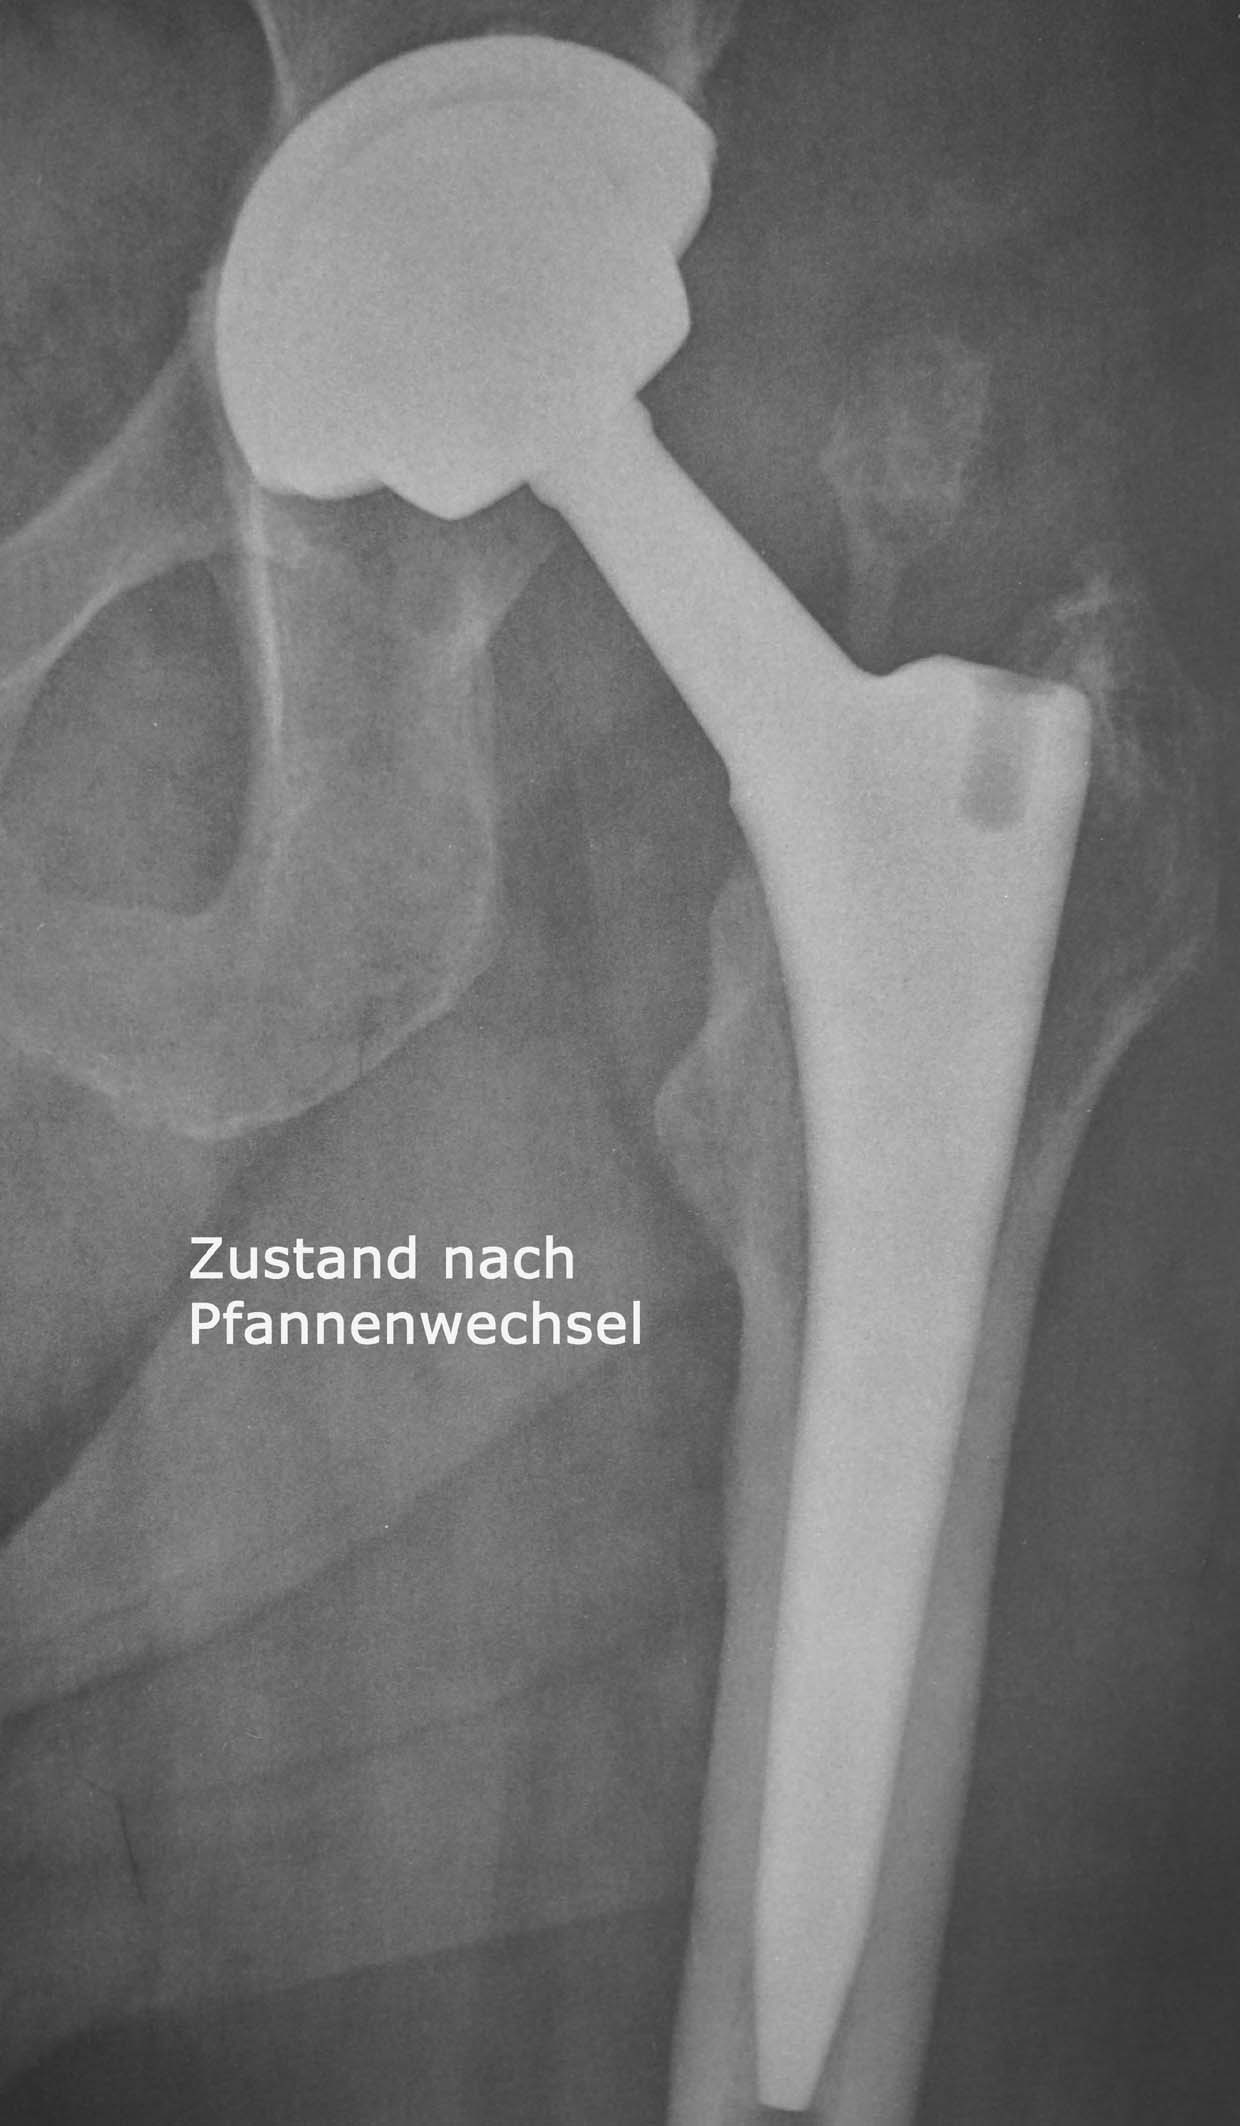

Hüftprothese

Die Hüftoperation bei Abnützungserkrankungen des Hüftgelenks wird in der übergrossen Anzahl der Fälle mit sogenannten zementfreien Prothesen durchgeführt , was bedeutet , dass die beiden Prothesenteile, also Pfanne und Schaft direkt in  Hüft und Oberschenkelknochen verankert werden können.

Dies ist zum einen durch passgenaue Fräsvorgänge der Knochen und zum anderen durch besondere Merkmale der Prothesenform selbst und der Oberflächen der Prothesen möglich. In Kombination mit der Keramik/Keramik Eigenpaarung , die für eine grosse Verschleißfestigkeit schon über Jahrzehnte bekannt ist ( siehe eigene Publikationen – Wissenschaftliche Tätigkeit) ist damit eine dauerhafte,stabile Verankerung und eine gute Funtion gewährleistet.

Bild anklicken zum Vergrössern